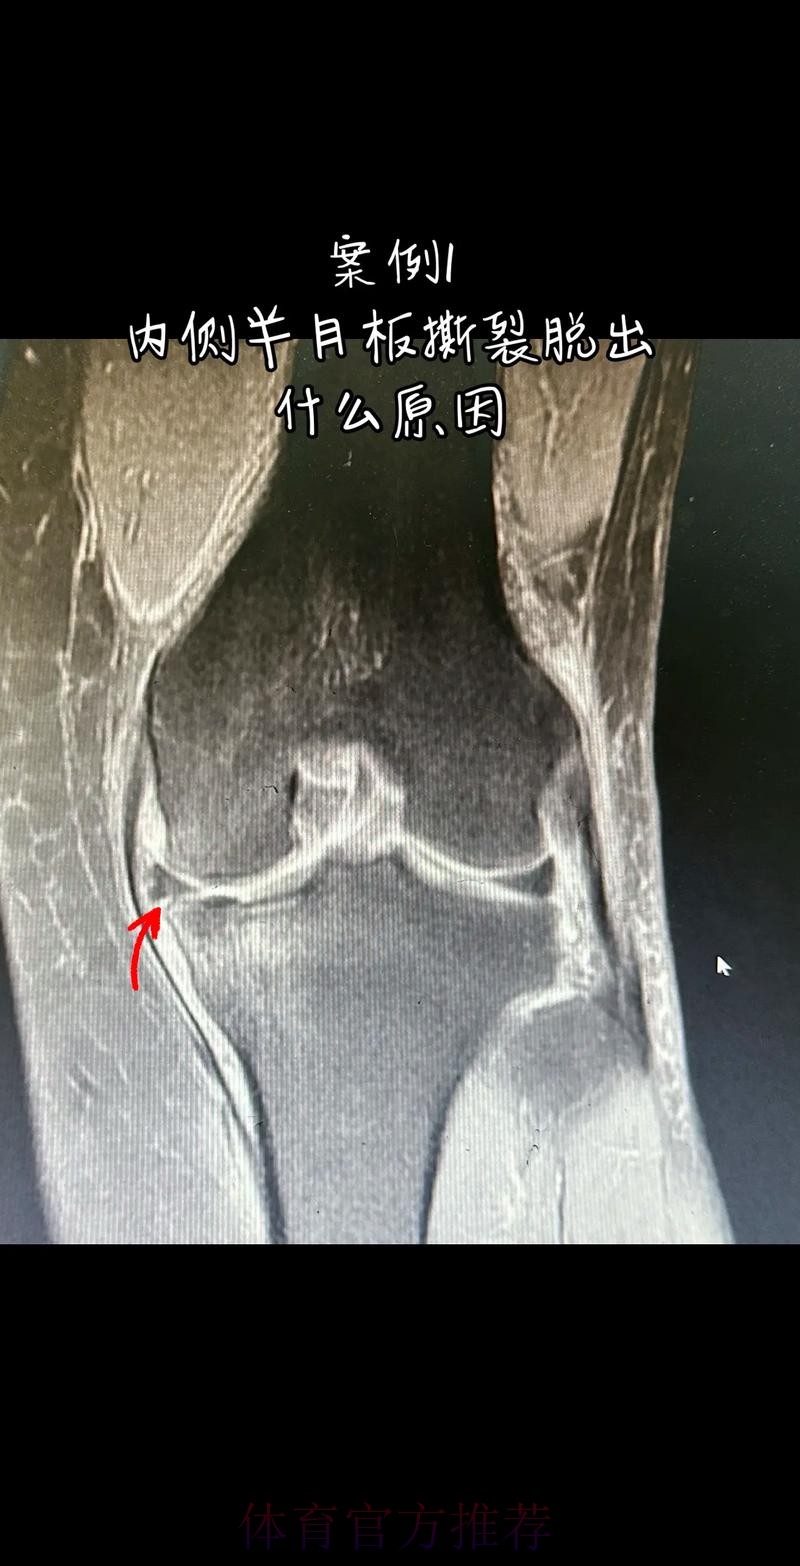

官方:阿拉巴左膝内侧半月板撕裂 预计伤缺6-8周

这条“官方 阿拉巴左膝内侧半月板撕裂 预计伤缺6-8周”的声明一出 不只是伤病通告那么简单 它背后牵动的是皇马后防体系的重塑 奥地利国家队备战计划的调整 以及一名顶级后卫职业生涯中一次关键的健康考验 对于已经习惯在高强度赛程中同时承担俱乐部与国家队重任的阿拉巴来说 这次伤病既是一次身体的警报 也是一次心理与战术层面的巨大挑战

在现代足球中 像阿拉巴这样能胜任中卫 左后卫 甚至后腰的多面手几乎是教练心中最理想的拼图 他不仅是后场的防守屏障 更是从后场发起进攻的节拍器 因此 当“左膝内侧半月板撕裂 伤缺6-8周”这样的诊断从官方口中给出时 对球队来说 就等同于在关键路段突然失去一块核心路基 球迷最直观的担忧是 皇马在这段时间是否还能保持防线稳定 奥地利是否在国际比赛日期间陷入被动 而对阿拉巴本人而言 这则官方消息意味着一个不得不按下暂停键的阶段 他需要重新面对恢复训练 康复计划 以及未来的竞技状态

阿拉巴在皇马的定位从来不只是“中后卫”这么简单 他可以在三中卫体系中担任左中卫 也可以在四后卫体系中出现在左后卫甚至拖后组织者的位置 在很多场次中 他会频繁前插 参与推进和组织 这意味着他在身体对抗 启动速度 横向移动和急停变向上的负荷都极高 半月板本身就处在运动生物力学的核心位置 当一名球员同时承担高强度防守和大量持球推进任务时 半月板承受的剪切力和压缩力都会显著增加 这也是为什么像阿拉巴这样“全能型”球员 更容易在高密度赛程中出现膝关节相关损伤

从医学角度看 半月板是膝关节内一块呈“C”形的软骨结构 其作用是缓冲冲击 稳定膝关节 并帮助分散压力 “左膝内侧半月板撕裂”通常说明在一次急停 旋转 或对抗中 半月板受到了超过其承受极限的力导致结构损伤 这类伤病常见于足球 篮球等需要频繁变向和对抗的项目 对于职业球员而言 半月板损伤严重程度不一 但共同点是都会影响支撑发力 跳跃以及变向时的稳定性 而官方给出的“预计伤缺6-8周”这个时间区间 往往对应的是中度损伤或通过微创手术加积极康复能够较快回归的情况 也意味着暂时没有出现必须长时间休战的最坏结果

表面上看 6-8周只是一个时间区间 但对顶级球队的赛程来说 这段时间可能包含多场联赛 甚至关键杯赛淘汰轮 相当于缺席一个赛季中最密集的一段周期 需要强调的是 这个“预计”并不是绝对数字 它取决于撕裂的位置 大小 修复方式 以及球员个体的恢复能力 有时若采取保守治疗 球员在6周时即可参与部分训练 但要达到比赛要求则可能接近8周甚至稍长 此外 精英运动员的康复不仅仅是伤口愈合 还包括力量恢复 协调重建 和心理自信的回归 阿拉巴要在有限时间内完成从“伤病患者”到“可靠首发”的角色转换 这一过程复杂程度远远超出一纸通告所能呈现